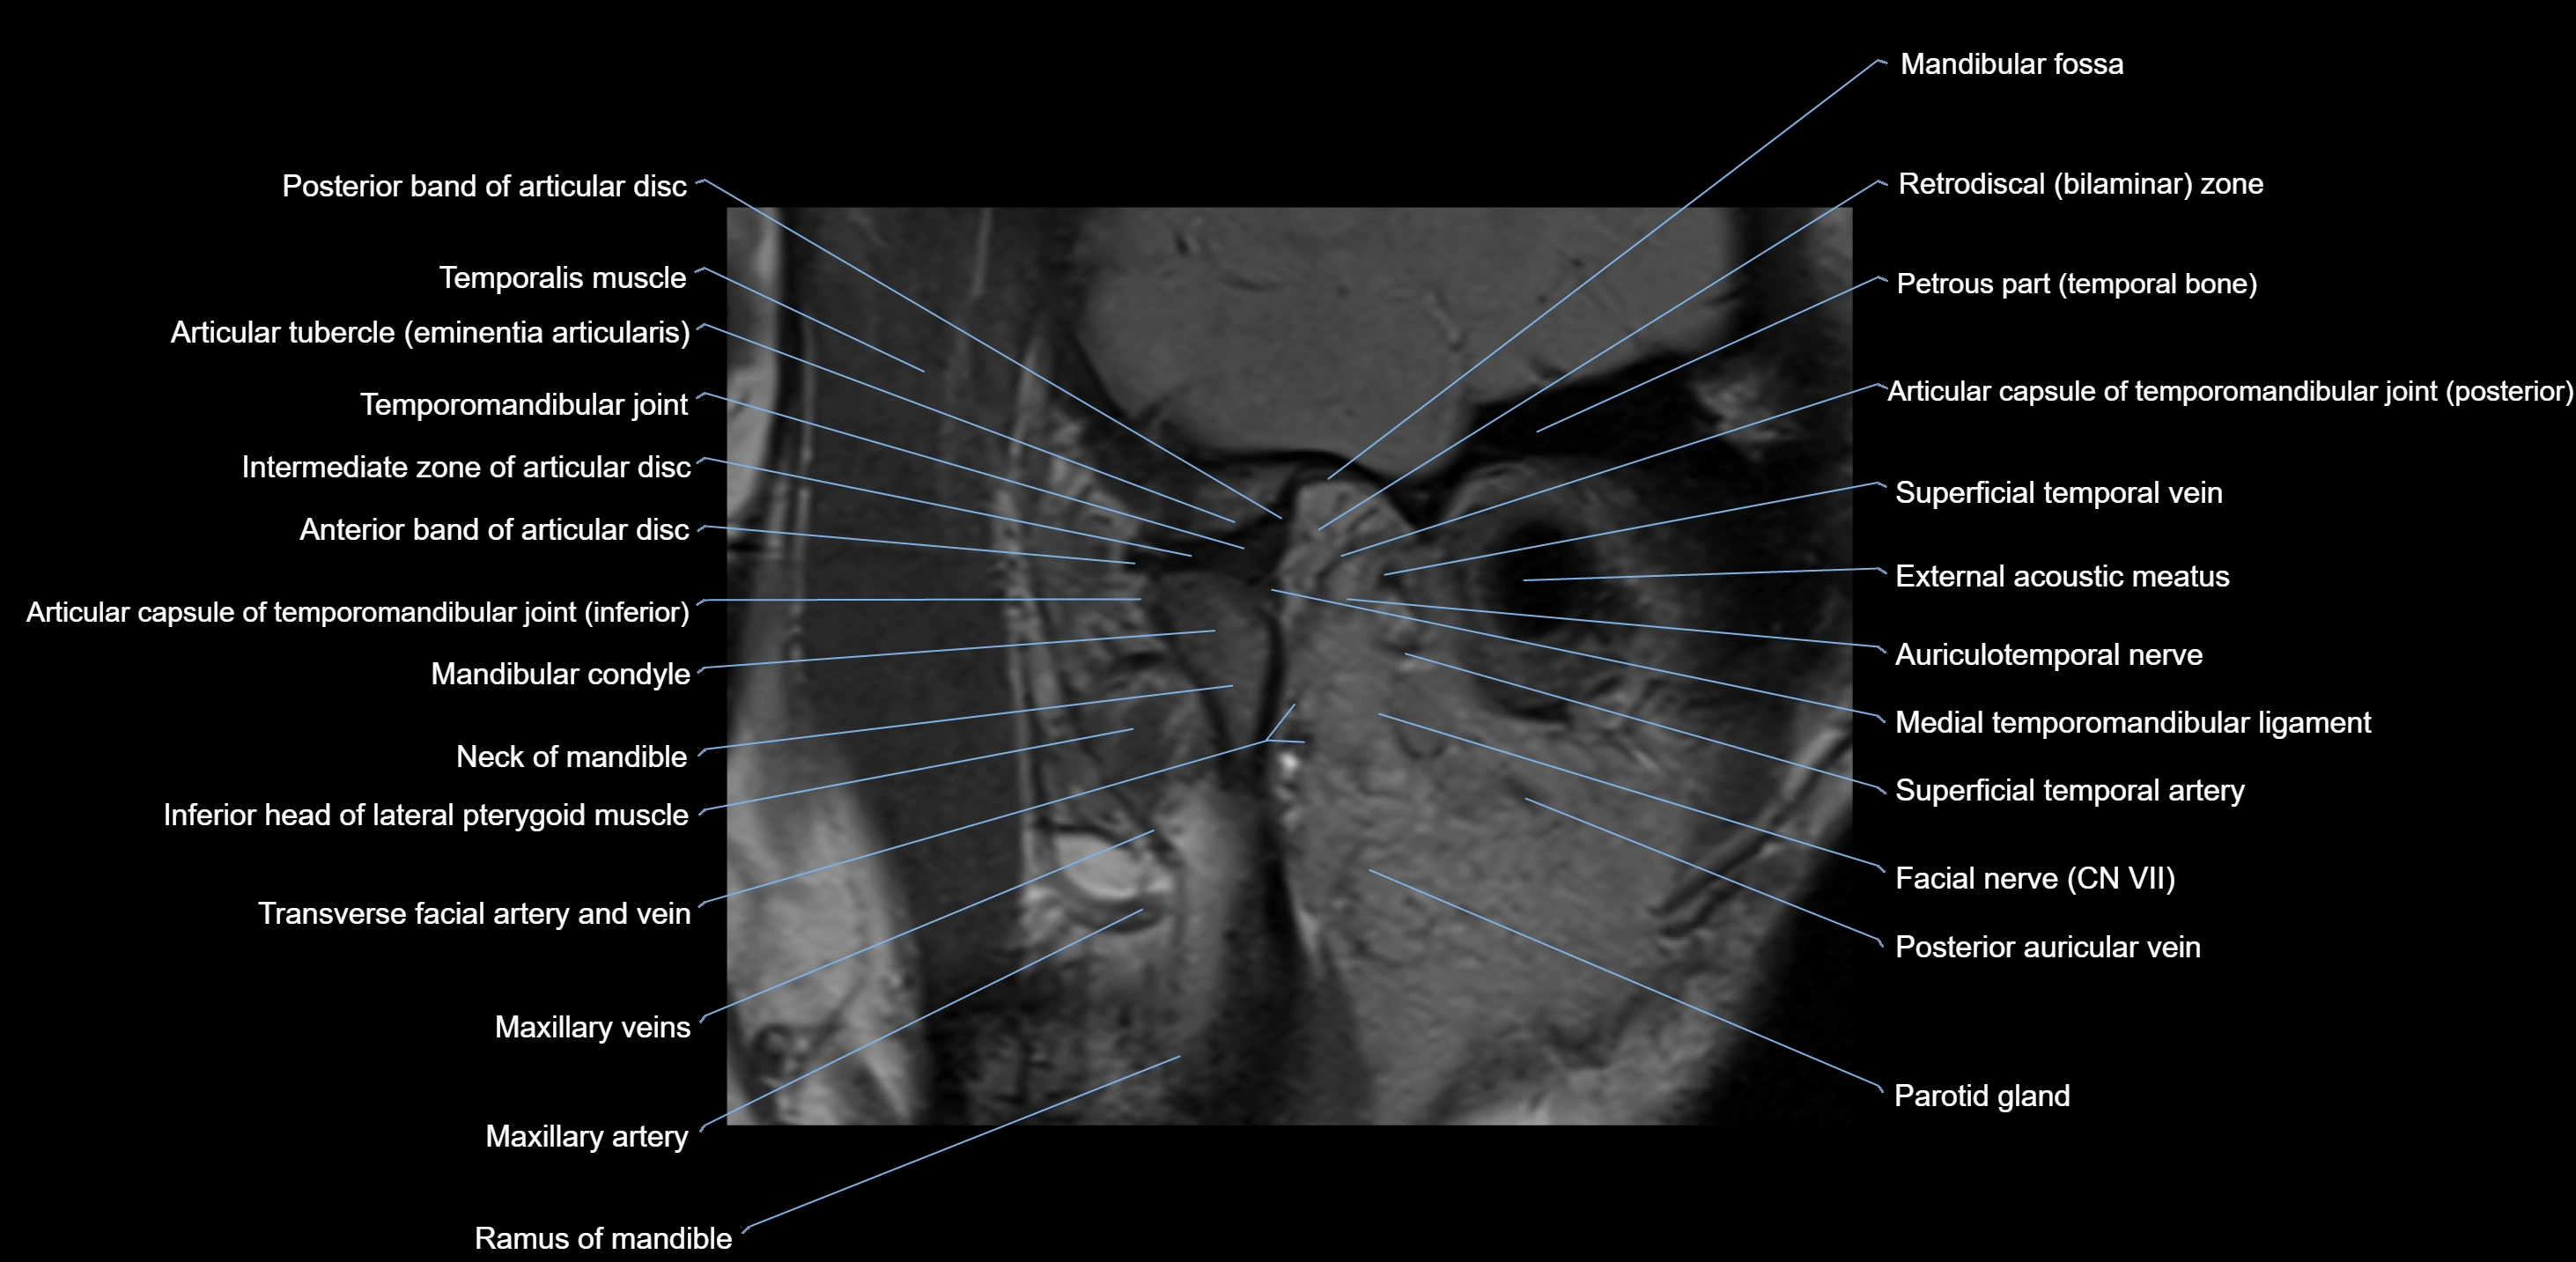

MRI appearance

T1-weighted images:

• Cortical bone: Low signal intensity

• Cancellous marrow: Intermediate to high signal depending on fatty content

• Teeth: Signal void structures

• Adjacent soft tissues: Normal gingiva and oral mucosa signal

T2-weighted images:

• Cortical bone and teeth: Low signal

• Marrow: Intermediate signal